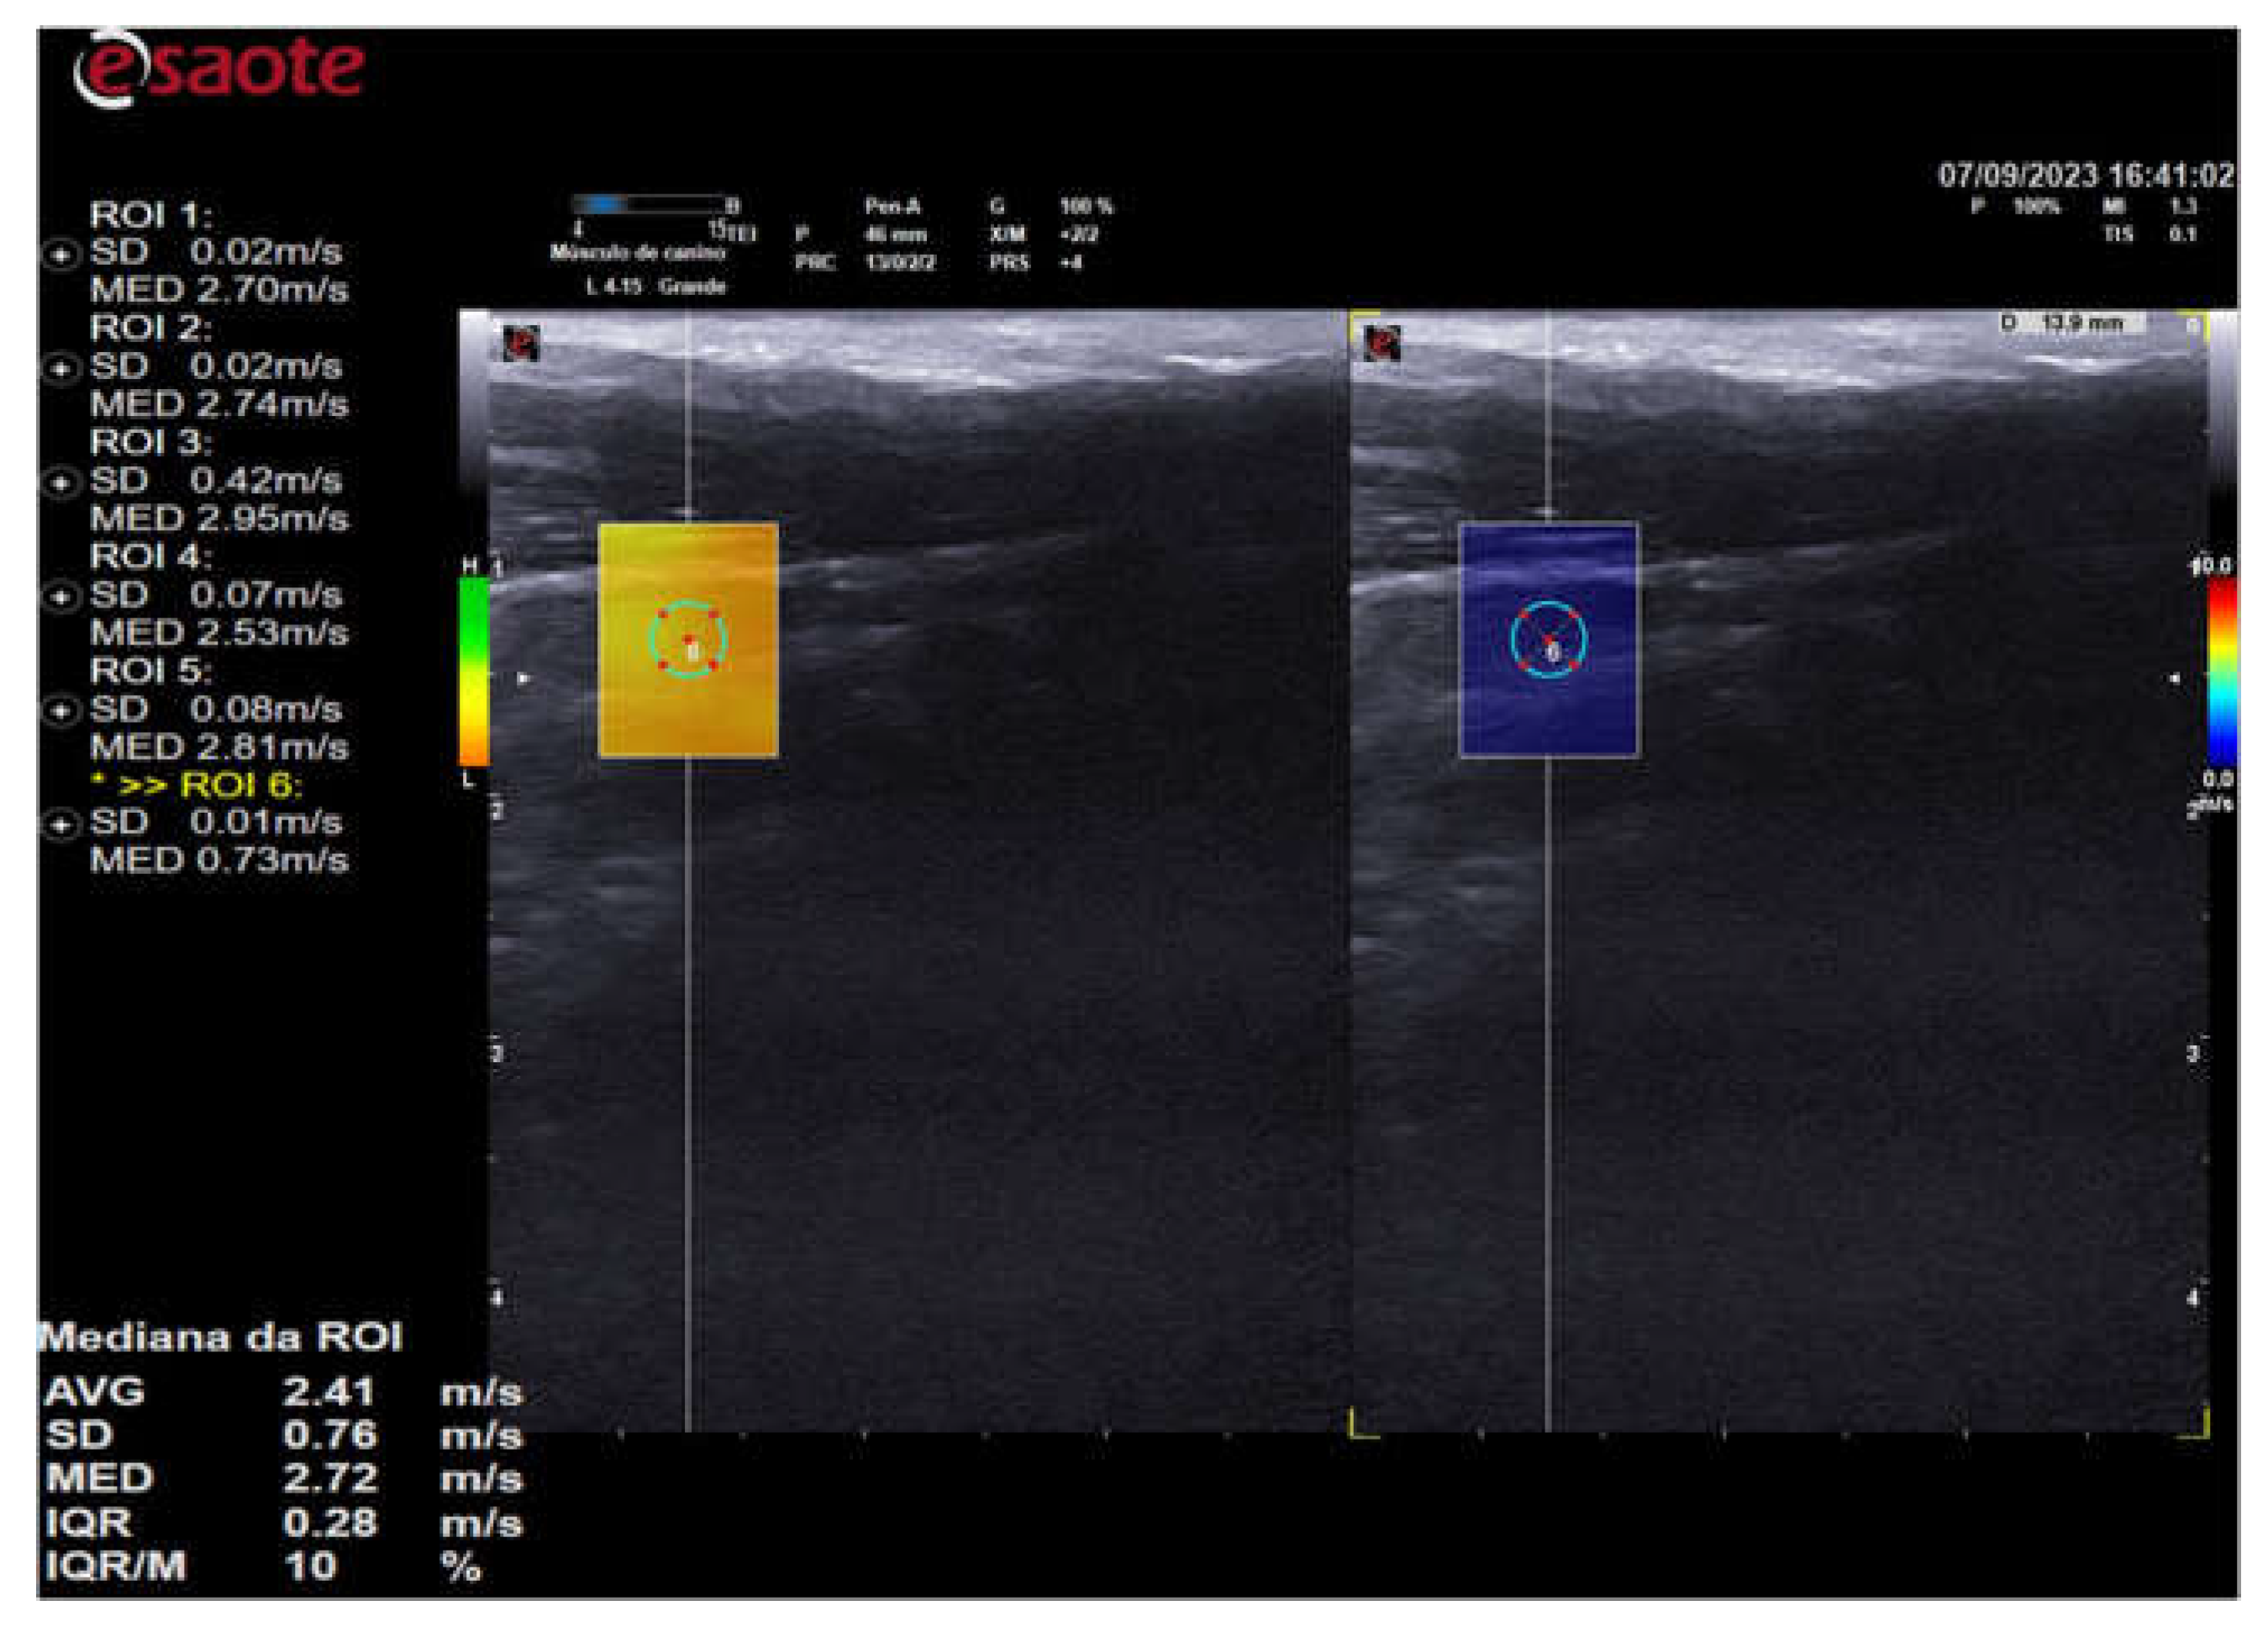

In all animals, shear wave velocity measurements were only taken in high-quality regions colored green. The stiffness scale of the color slastogram ranged from blue (soft/soft) to red (stiff/hard), passing through green and yellow (intermediate stiffness). To assess stiffness using shear wave velocity, 5 (five) samples (areas of interest - ROI's) were randomly selected, comprising different portions of the thyroid using 0.2cm diameter circles as shown in Figure 5. The shear wave velocity values of the analyzed portions were evaluated by the equipment's software and expressed in m/s.

Figure 5. - 2D shear wave elastography image of the right thyroid lobe of a 10-year-old dog. Elastographic image on the left showing the QelaXtoTM 2D software quality map colored in green, indicating high quality for measuring shear wave velocity (quantitative) and selection of four ROIs for measuring shear wave velocity. Right side of the elastographic image showing the color elastogram (qualitative) from the QelaXtoTM 2D software colored in blue, indicating that the thyroid parenchyma had low rigidity (soft/soft).